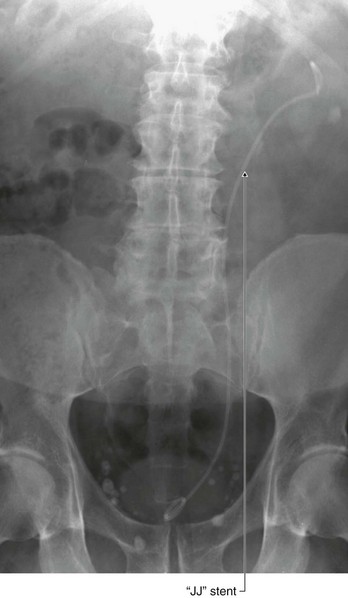

A nephrostomy is a procedure where a tube is placed through the lateral or posterior abdominal wall into the renal cortex to lie within the renal pelvis. The function of this tube is to allow drainage of urine from the renal pelvis through the tube externally (Fig. 4.145).

Fig. 4.145 This radiograph, anterior-posterior view, demonstrates a double J stent. The superior aspect of the double J stent is situated within the renal pelvis. The stent passes through the ureter describing the path of the ureter, and the tip of the double J stent is projected over the bladder, which appears as a slightly dense area on the radiograph.

The kidneys are situated on the posterior abdominal wall, and in thin healthy subjects may be only up to 2–3 cm from the skin. Access to the kidney is relatively straightforward, because the kidney can be easily visualized under ultrasound guidance. Using local anesthetic, a needle can be placed, under ultrasound direction, through the skin into the renal cortex and into the renal pelvis. A series of wires and tubes can be passed through the needle to position the drainage catheter.

The indications of such a procedure are many. In patients with distal ureteric obstruction the back pressure of urine within the ureters and the kidney significantly impairs the function of the kidney, which will fail to function. This will produce renal failure and ultimately death. Furthermore, a dilated obstructed system is also susceptible to infection. In many cases, there is not only obstruction producing renal failure but also infected urine within the system.